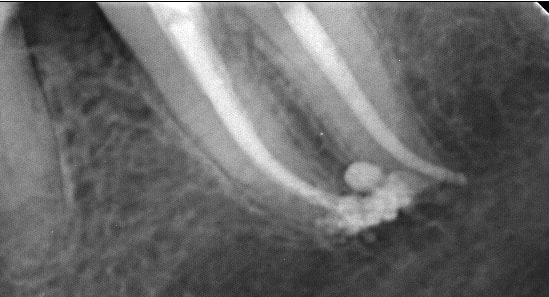

Je m'entraine au mac spaden mais abrès avoir réalisé des bouchons apicaux au friendo ( enfin j'essaye par ce que ca bloque un peu trop loin de l'apex vu que je n'ai pas toutes les tailles d'inserts lol !); Pas franchement de meilleure image qu'au monocone scellé.

Je me fais chier pour rien je pense mais j'appréhende cet engin qui tourne à 40 000 tours ( j'utilise le diametre 40 pour une préparation au R25)

Ca compacte dur par contre vu que l'intégralité du cone ( ici un diametre 40) disparait dans le canal.

En termo-compaction pure à combien de mm de l'apex faut il envoyer l'engin ? vu la pression que ca développe une connerie est vite arrivée.

pas cool de commencer par une 36 de 4 canaux. Par contre.)))))))

R1 iqqn0y - Eugenol

R2 sxl3pa - Eugenol

R3 ulnhut - Eugenol

R4 hefdnh - Eugenol

Loop trrma6 - Eugenol

En thermocompaction faut se tenir à 4mm de l'apex (a peu pres). Et même si on voit pas tout le temps la différence radiologiquement avec le monocone, on est sur que c'est étanche à l'apex (ce qui est pas du tout le cas avec un monocone scellé...)

PS: belle obtu ;)

Oui c'est la meme chose avec le système B utilisé (friendo de hufriedy). Seulement j'ai pas réussi à descendre les inserts à 4 mm de l'apex (trop gros taille FM/06) curieux d'ailleurs dans certains canaux je n'en suis pas loin. Mon obturation est donc en monocone scellé au bout.)))))

Pour un alésage en 25 /06 quel diametre utiliser ?

Un compacteur de 30. Les revo condensor sont parfait ils ont une bague violette. Je ne me sers presque que de ces thermocompacteurs. La densité des cônes compactes à la radio dépend de leur concentration en eugenol.donc peu significatif. Pour me faire la main je passais le cone puis un.coup de finger spreader et après seulement le compacteur

Juste pour prouver qu'on peut tout faire avec Mc Spadden, le derviche écossais:

Canal large, on est allé au F5 sans toucher les bords, cône calibré à 55 à l'apex, thermocompacteur à 3mm de la LT. Pas d'anesthésie.